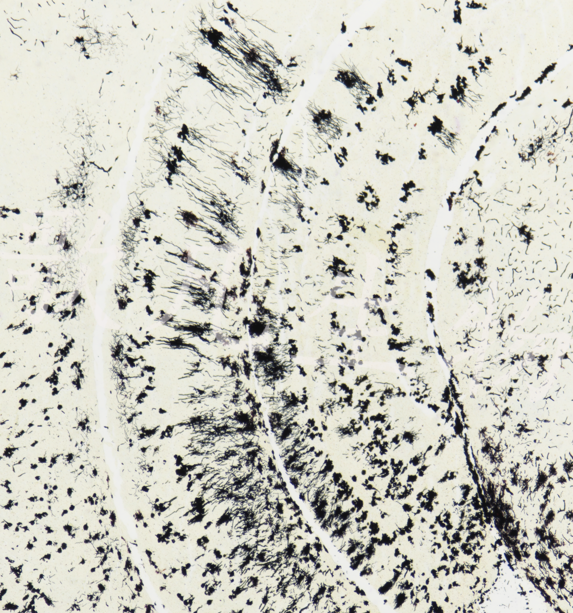

Golgi氏神经元神经纤维染色试剂盒说明书

神经纤维是由神经元的轴突和树突等成分组成,经过银染后再用还原剂处理,使银颗粒沉着于纤维和细胞中.

神经元及神经纤维的染色方法种类较多,但大多采用镀银法.常用于神经组织疾病的诊断和研究.

神经元胞体及突起呈黑色或黑红色。